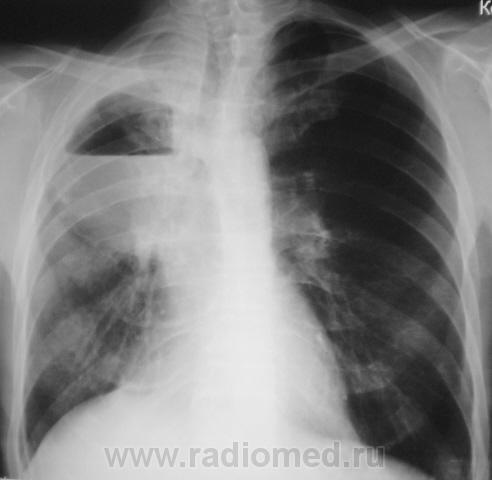

Просьба оценить динамику.

После лобэктомии.

Снимки - два этапа - до лобъектомии и после лобэктомии (верхняя доля) правого лёгкого).

Конечно, выставленное с такой манере может показаться весьма странным. Фактически это "хвост" случая, который закончился (на настоящее время) резекцией доли справа (верхняя). Хотя сейчас, многими докторами "высокой клиники" высказываются мнения, что все могло быть иначе, менее "кроваво", если-бы во-время и своевременно, и если-бы не тянули...